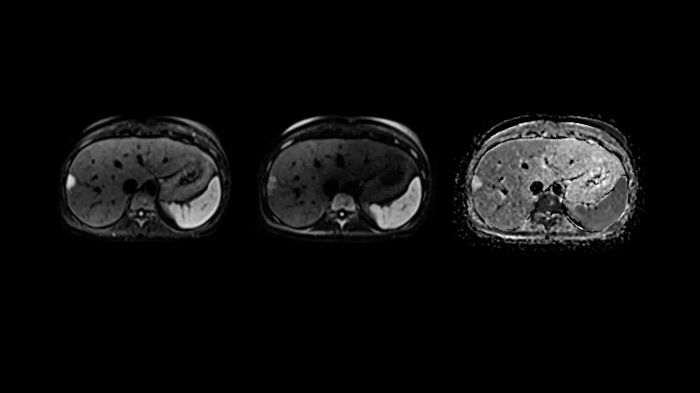

Body diffusion imaging

Outstanding quality diffusion imaging for comprehensive abdominal MR capabilities.

- Contour L Coil

- Spine Coil

Image Courtesy: University Hospital Erlangen, Germany | Image-ID: 4aaaa0339